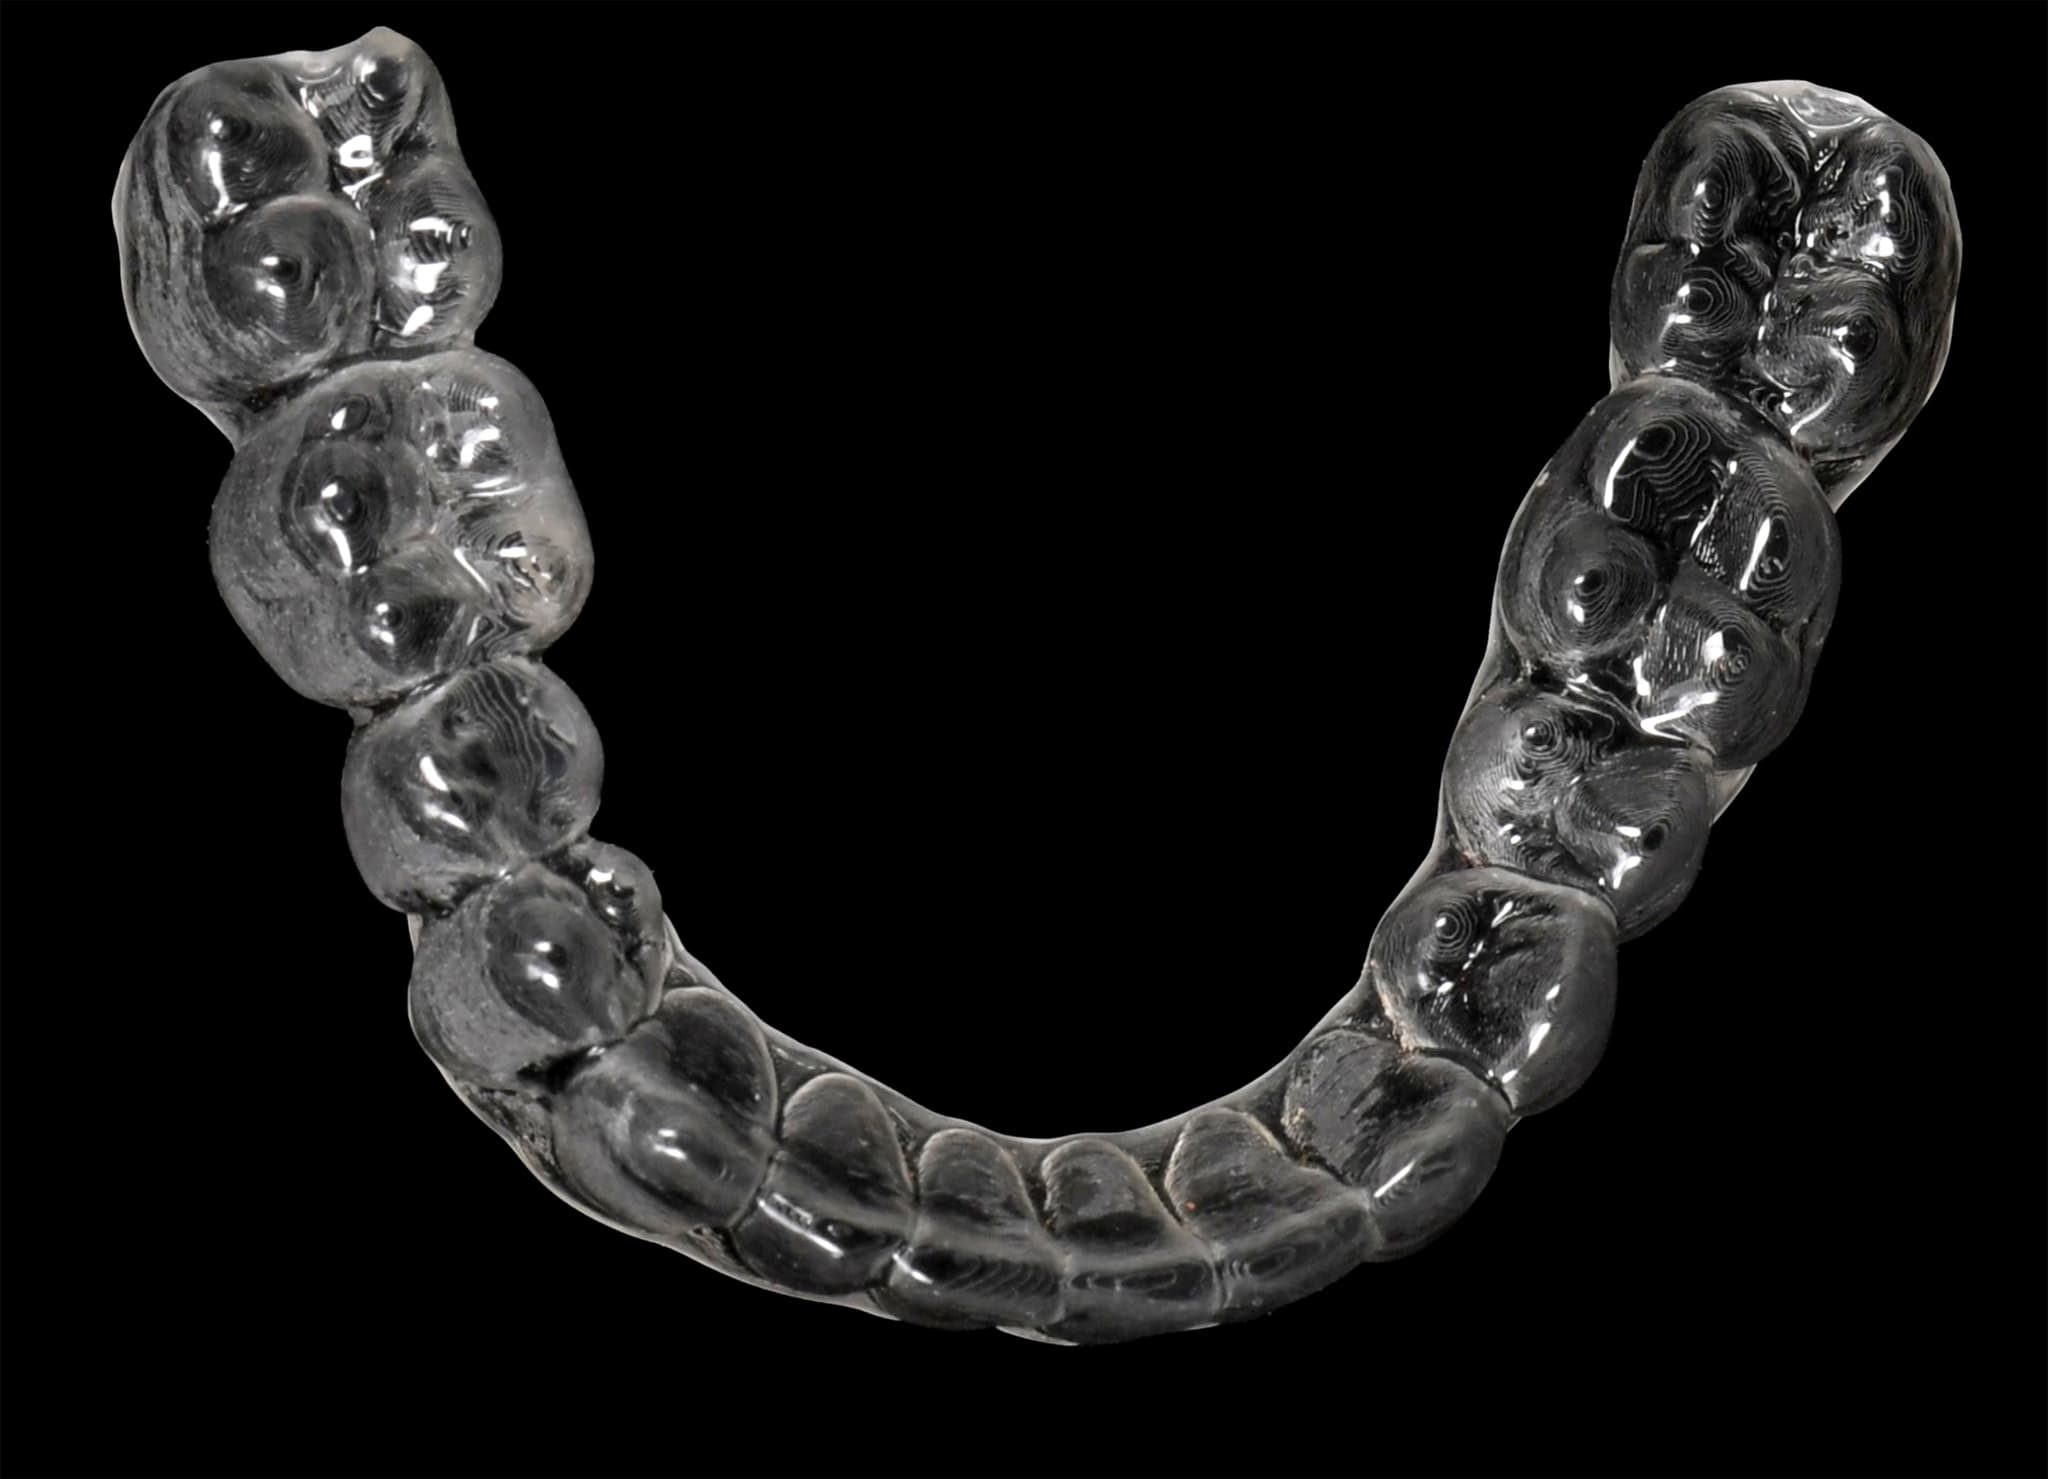

După atingerea poziției finale, rafinăm detalii precum liniile mediane, punctele de contact și arcul zâmbetului. Guttierele de contenție sunt concepute pe baza planului digital final. Fiindcă întregul caz este arhivat, eventualele ajustări sau restaurări viitoare rămân aliniate cu designul inițial—chiar și peste ani.